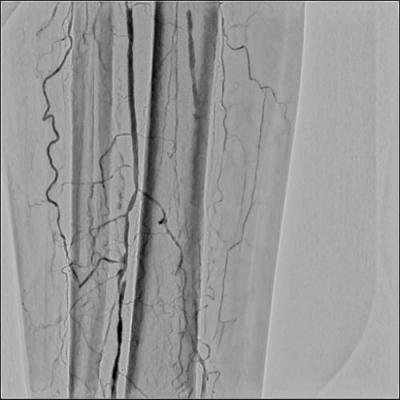

血管内治療 (Endovascular therary ; EVT)

カテーテル治療と以前呼ばれていたものですが、近年はEVTとの呼び方が一般的です。カテーテルを動脈内に挿入し狭いところや閉塞したところで風船をふくらませ、場合によりステントを置いて再び狭くなるのを防ぎます。多くの患者さまは2泊3日入院で行っており、患者さまの負担も少なく入院期間も短くてすみます。また、単に風船で行うだけでなく、治療後再狭窄を予防するための薬剤溶出性バルーンや薬剤溶出性ステント、ステントグラフトといった最新式の新規デバイスの適応を考慮し適切に使用しています。これらの活用により非常に再狭窄の少ない良好な治療実績を得ています。

カテーテル治療の実際

カテーテル治療前

カテーテル治療後